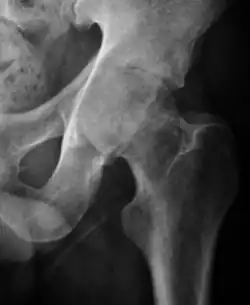

Plain radiography allows us to categorize the hip as normal or dysplastic or with impingement signs (pincer, cam, or a combination of both). Besides these, pathologic processes like osteoarthritis, inflammatory diseases, infection, or tumors can also be identified (Figure 1).[1]

Figure 1.

-

Radiography in normal hip -

X-ray in pincer impingement type of hip dysplasia -

X-ray of cam -

Hip in osteoarthritis -

Septic arthritis